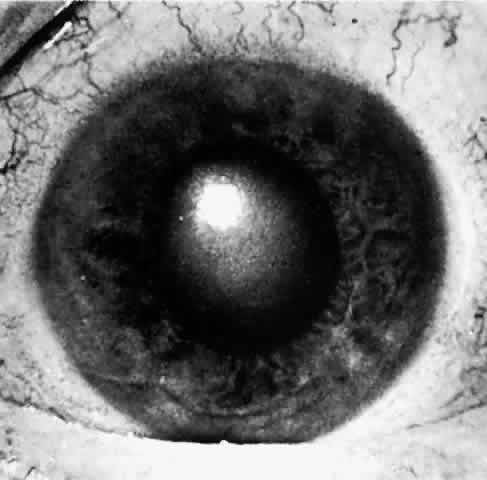

If gonioscopy is obscured by corneal epithelial edema, application of topical 100% glycerol on the anesthetized cornea will often clear the edema sufficiently to permit adequate visualization of the peripheral anterior chamber and angle structures. During an attack, one sees only the cornea and iris meeting directly, with no evidence of the angle entrance or angle structures (Figs. 7 and 8). Indentation gonioscopy, introduced by Forbes,34 may be useful to differentiate between appositional and synechial closure of the angle. Central compression with a four mirror gonioscopy lens on the central cornea pushes the central aqueous to the peripheral anterior chamber. This maneuver pushes the peripheral iris posteriorly and opens an appositionally closed angle. If peripheral anterior synechiae are present, the angle will not be opened with indentation. The lower the initial pressure, the easier the examination. If the pressure is extremely high, indentation gonioscopy is extremely difficult, painful, and the cornea may be too edematous to allow visualization. If despite corneal dehydration with glycerol, edema of the affected eye precludes clear gonioscopy, examination of the angle structures of the fellow eye is often helpful. An extremely narrow closeable angle is usually present in the fellow eye giving strong evidence to the diagnosis of angle closure of the affected eye. Funduscopic examination is usually of little value because it is commonly precluded by corneal edema. When possible, early ophthalmoscopy shows pulsation of the retinal arterioles.

Fig. 7. In this goniophotograph, the angle is moderately wide open. As one looks just anterior to the edge of the peripheral iris (arrow), one sees the dark ciliary band, white scleral spur, and trabecular meshwork, which is moderately dark and pigmented in this eye. Schwalbe's line anterior to the trabecular meshwork is not visible in this photo. Such an angle is much too wide to be susceptible to primary angle-closure glaucoma.

Fig. 8. In contrast to Figure 7, this angle is closed. At the arrow, one sees the edge of the peripheral iris. The ciliary band, scleral spur, and trabecular meshwork are covered by peripheral iris, and one sees only cornea anterior to it. This could be reversible appositional closure of the angle of permanent synechial closure.